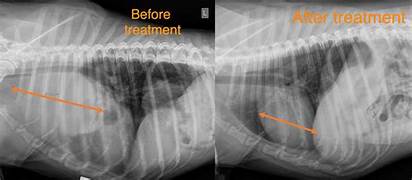

- Imaging: X-rays or ultrasound may be used to examine the chest, abdomen, or other areas where lymphoma might be present. These imaging techniques can help detect swollen lymph nodes or masses in the organs.

Diagnosing lymphoma in pets typically involves a multi-step process to ensure accuracy and to rule out other possible conditions. A veterinarian will start with a physical examination, palpating lymph nodes to detect any swelling and assessing the pet’s overall health. Blood tests may follow, as lymphoma can cause changes in the blood, such as elevated white blood cell counts or anemia, which may indicate an underlying issue. Imaging techniques, such as X-rays or ultrasounds, are crucial for examining areas where lymphoma may have spread, including the chest, abdomen, or spleen. However, the definitive diagnostic tool for lymphoma is a biopsy. In this process, a sample of tissue from an enlarged lymph node or mass is taken using a fine needle aspiration (FNA) or a more invasive biopsy procedure. The collected tissue is then analyzed under a microscope to check for the presence of malignant lymphocytes. If lymphoma is confirmed, staging the cancer becomes essential. Staging involves determining the extent of the disease, whether it’s localized to a particular area or has spread to other parts of the body. The most common staging system is a 5-stage scale, ranging from stage I (localized) to stage V (involving vital organs like the bone marrow or liver).